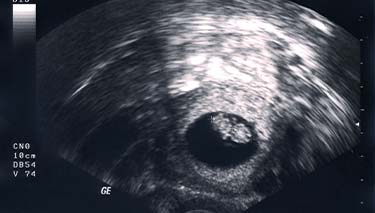

The ultrasound will pick up images of your baby's organs in a series of cross sections. This can be confusing at first, until you become used to the images and your eyes adjust. Your baby's bones will be white on the screen and the amniotic fluid will appear as black. Their tissues will be grey and have a speckled appearance.